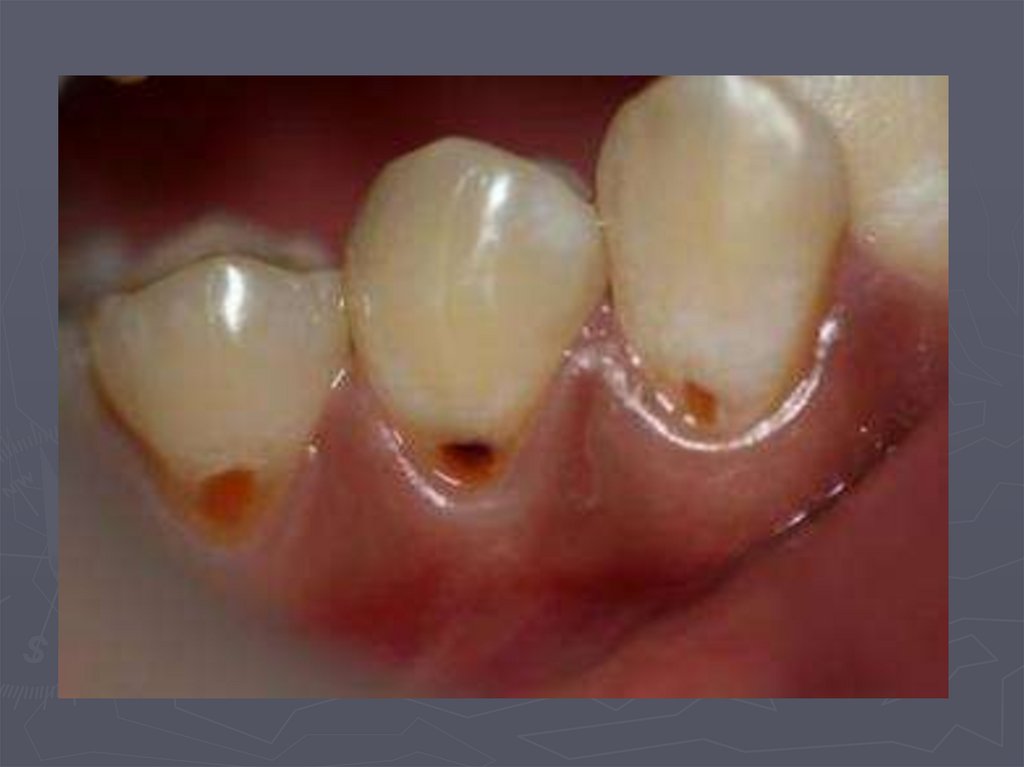

92. МЕТОДЫ ДИАГНОСТИКИ КАРИЕСА У ДЕТЕЙ

РЕНТГЕНОЛОГИЧЕСКИЙ МЕТОД –

применяется:

в случаях крайнего затруднения

диагностики,

► при локализации полостей на

апроксимальных поверхностях,

► при тесном положении зубов.

93. Кариес на рентгеновских снимках